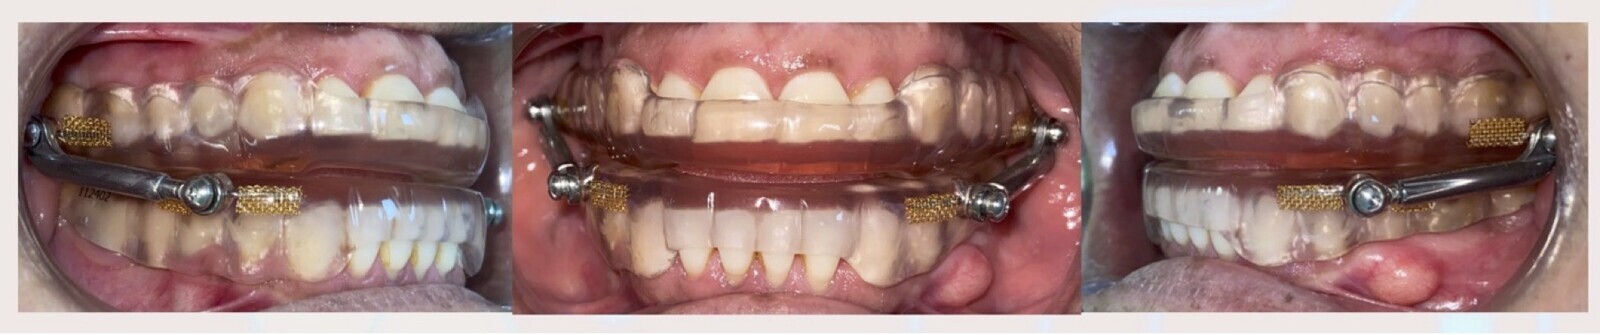

Figura 1. Paciente femenina con Apnea del Sueño referida a nuestra clínica para la fabricación de un DAM personalizado. Fotos: Salvador Romero Triana

Paciente femenina de 60 años con diagnóstico de Apnea del Sueño moderada referida de El Paso Sleep Center en Estados Unidos (Figura 1) a nuestra clínica en Ciudad Juárez, México, para la fabricación de un Dispositivo de Avance Mandibular personalizado.

En el diagnóstico dental se observan en radiografías y tomografías una excelente condición periodontal y radicular para el soporte del Dispositivo de Avance Mandibular, así como vías aéreas estrechas a nivel de la faringe (Figura 2).